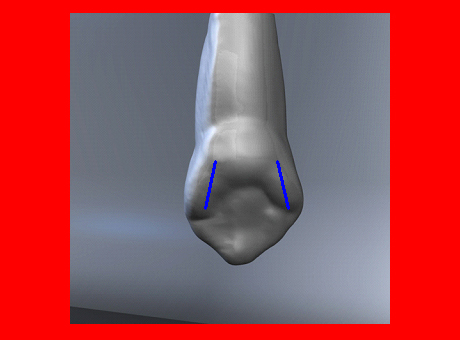

En ciertas áreas del saber humano, el lenguaje confuso o criptográfico Muchas son las técnicas elaboradas para lograr un desgaste selectivo, y numerosos autores han expuesto en su momento variadas formas de lograr una función oclusal fisiológica mediante el ajuste de la misma. Han pasado años desde entonces y, sin embargo, aún hoy, un altísimo porcentaje de profesionales “navega” por el mar de la confusión oclusal, dada la diversidad de conceptos y escuelas, sin lograr arribar a costa alguna donde poder anclar un conocimiento sólido sobre cómo tratar la oclusión Ya se esté realizando una simple obturación, endodoncia, incrustación, radectomía u ortodoncia, la lógica pocas veces, en la mayoría de los casos, vincula un tratamiento con otro, siendo el resultado final el mismo caos inicial; enmascarado por mucho tratamiento profesional. El ajuste oclusal es un medio inicial de proveer al sistema enfermo de: Dicha técnica, que puede ser terapéutica en sí misma; consta de dos etapas, a saber: 1) Ajuste Oclusal por Adición Mediante el estudio de la guía anterior, encargada de efectuar las Disclusiones durante las excursiones mandibulares, podremos observar si ésta es funcional o no. • Marcas de carácter continuo, si en ese recorrido se produce la Disclusión de los sectores posteriores y todo marcha correctamente. FIG 1-2 Si por el contrario observamos: • Marcas de carácter discontinuo, significa que dicha Disclusión se está efectuando por medio de una pieza dentaria posterior a la guía anterior. FIG 3-4-5 (FIGS. 3, 4 Y 5). En la figura 6 las flechas indican, en un caso clínico de análisis oclusal, la presencia de marcas discontinuas que indican Interferencias en Propulsiva. FIG 6-7 Y por último, si existieran: • Abrasiones de las áreas discluyentes en las áreas de diagnóstico de la guía anterior, deberemos aportar material a dicha zona para no permitir el choque lateral de las piezas posteriores (Ajuste Oclusal por Adición) En las imágenes 11 y 12 podemos observar la adición de composite en la punta de un canino derecho, previa la observación de la Faceta Parafuncional remarcada durante el análisis oclusal en el articulador. (FIGS. 8 A 12). 2) Ajuste oclusal por Sustracción o Desgaste Habiendo cumplido ya con la verificación de la funcionalidad de la Guía Anterior, comenzamos los desgastes en céntrica, a fin de lograr un único arco de cierre, guiado eficazmente por la Guía Anterior; es decir: la coincidencia entre Oclusión Habitual y Oclusión en Relación Céntrica. En este caso, intentar gastar dichos puntos, de ser posible sólo en las cúspides de corte o no fundamentales: • Crestas Triangulares Internas, Cúspides Vestíbulares Superiores • y un poco de las Crestas Triangulares Internas, Cúspides (FIGS. 13 A 16). Si la deflección es hacia el lado opuesto, se invierten los desgastes. En las migraciones hacia adelante, las únicas razones posibles están en los puntos estabilizadores (FIG. 17); es decir: -Vertientes Distales de los Rebordes Marginales, Triangulares (FIG 17) (FIG 18 A-B-C-D) Obsérvese cómo, en una boca prácticamente entera, comienzan a “desmoronarse” prismas adamantinos (FIG. 19), como consecuencia de un punto prematuro de contacto, ubicado en la posición de un estabilizador, que provoca la discrepancia horizontal postero-anterior causante de dicho efecto (FIG. 20). FIG 19-20 Dicho punto, será necesario ajustarlo antes de cualquier tratamiento en la zona ¿Cuáles serían las consecuencias si esos incisivos fueran implantados tal como es frecuente observar en múltiples congresos y cursos de implantología, donde el tema de la oclusión no es más que un cuadro polifacético y anecdótico? 14 15 16 17 Todo producto del adelantamiento mandibular Realizados ya los desgastes en céntrica, obteniendo de esta manera un único arco de cierre, es decir, oclusión en relación céntrica, debemos realizar el ajuste de las excéntricas, apoyando la acción de la guía anterior, para lo FIG 22 a. De un lado a otro de un mismo maxilar, la imagen es especular, o sea invertida. b. En hemimaxilares cruzados, la imagen es idéntica. Allí donde existan colisiones entre cúspides, se deberá crear un surco para que dicha cúspide antagonista migre a su través, tanto en el lado de no trabajo, como en el de trabajo y en el de propulsión. FIG 23 Es importante conservar esta parte del surco, ya que si no existieran, los contactos entre cúspides serían en superficie y no puntiformes (fig. 24). FIG 24 1. Obtener un único arco de cierre con coincidencia entre oclusión habitual y relación céntrica. 2. El cierre mandibular debe ser recibido sólo por la tabla premolar-molar. 3. Durante las excursiones funcionales es la guía anterior la que debe sufrir las fuerzas laterales. 4. De cumplirse estas dos premisas debemos obtener libertad de desplazamiento (no confundir con libertad en céntrica) a las piezas posteriores mediante la creación de surcos disclusivos. Examinadas ya las posibles migraciones mandibulares y los desgastes o aposiciones necesarios para poder ocluir en céntrica, es fundamental recordar que, previamente a todo tipo de ajuste, se ha hecho necesario ubicar a la mandíbula en relación céntrica. Para ello debemos utilizar el propio funcionalismo muscular 22 FIG 25 Y esto no significa otra cosa que: piezas dentarias estables en todos los planos del espacio, ATM centrada en la cavidad glenoidea, periodontos sin tensión, músculos en la dimensión de elongación adecuada para un fisiologismo Paz absoluta en la intimidad del Sistema Estomatognático. Y así, como corolario final, es posible establecer una regla de oro similar en importancia a la conocida formula: Forma = Función Ésta es: FIG 26 FUNDAMENTOS NEUROFISIOLÓGICOS DEL REGISTRO DE OCLUSIÓN EN RELACIÓN CÉNTRICA ( ORC) MEDIANTE EL USO DE LAMINILLAS DE LONG CUADRO

En el transcurso de dichas Lateralidades o Propulsiva, podremos ver:

En la figura 7, se muestran la Disclusión Inicial (durante el transcurso de la cual deben separarse por completo los sectores posteriores –flecha izquierda–, y la Disclusión Final de recorrido mucho más largo –flecha derecha–.